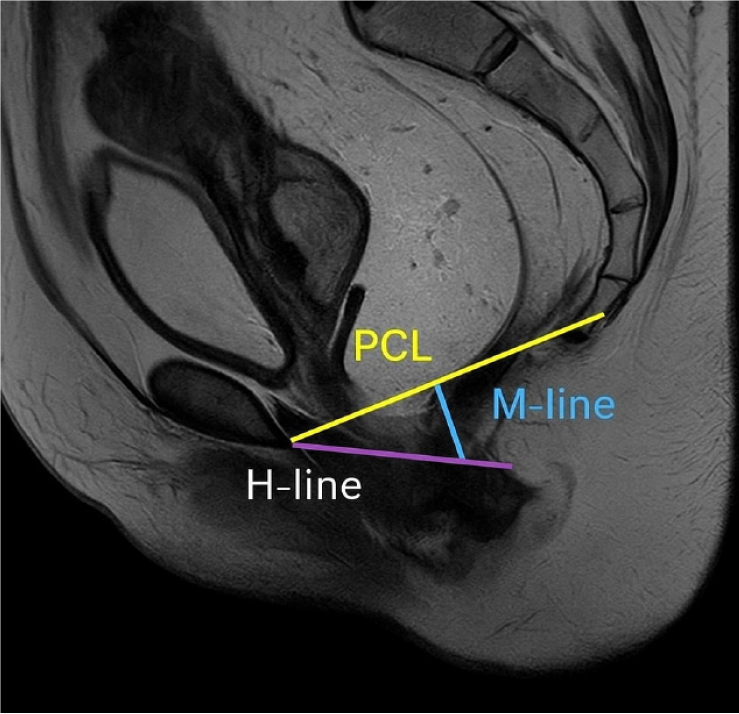

Figure 1 Magnetic resonance defecography T2-weighted image depicting the normal pubococcygeal line[14].

Pubococcygeal line (PCL) (yellow line) spans the inferior border of the pubic symphysis to the last visible coccygeal joint. H-line (purple) represents the length of the anterior-posterior levator hiatus. M-line (blue) measures the vertical descent of the anorectal junction below the PCL. Citation: Korula DR, Chandramohan A, John R, Eapen A. Barium Defecating Proctography and Dynamic Magnetic Resonance Proctography: Their Role and Patient's Perception. J Clin Imaging Sci 2021; 11: 31. Copyright ©The Author(s) 2011. Published by Scientific Scholar LLC (Supplementary material).